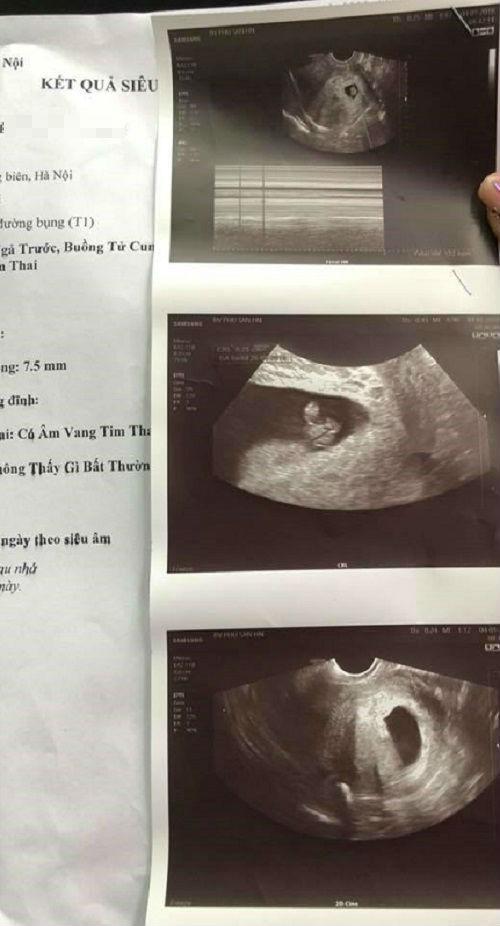

Khi sang BV Phụ sản Hà Nội, tôi được đưa vào siêu âm đầu dò. Kết quả, con tôi bình thường không làm sao, chỉ hơi bị động thai và bác sĩ kê thuốc về nhà vừa uống, vừa nghỉ ngơi theo dõi, đồng thời hẹn 2 tuần sau đến khám lại.

Hình ảnh và kết luận của bệnh viện PS Hà Nội cùng 1 ngày với bệnh viện Đức Giang, khẳng định thai vẫn bình thường.